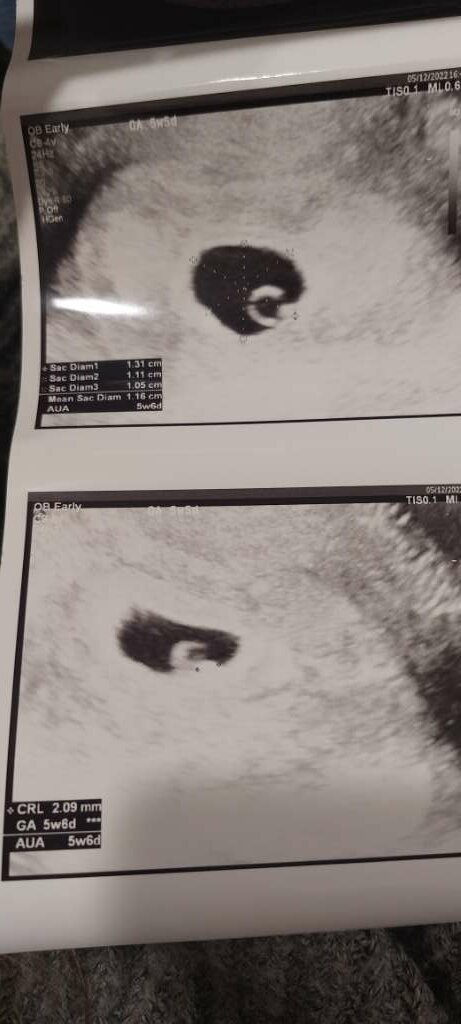

Tak to u mnie wygląda